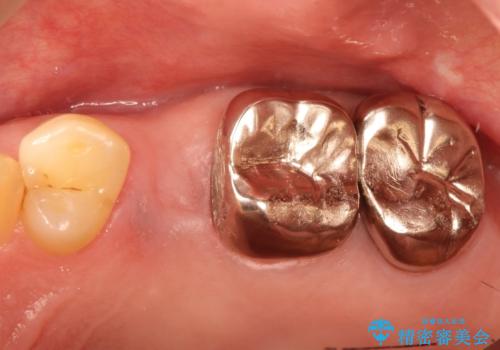

小臼歯部のインプラント

- 他院にて└5の治療を繰り返しても痛みがなくならないことを主訴に来院されました。

患歯はすでに2回の歯根切除術を受けており、長期的な予後不良となることから抜歯を選択されインプラントによる治療を行いました。

└6の不良補綴物も認め、根管治療及び補綴もやり替えてます。